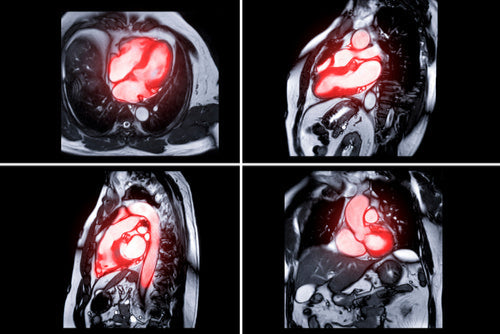

Cardiac magnetic resonance imaging (cardiac MRI)

What it is and how it works: A cardiac MRI is an investigation used to take high-resolution images of the heart using a powerful magnet. Unlike a chest x-ray or CT scan, an MRI does not use x-rays. However, it is very important to remove any metal objects before having the test. During a cardiac MRI, you will be asked to lie down on a table before being moved inside of the machine. It can get quite noisy during the test, however you will be provided with headphones or given the option to listen to some music. You may be asked to hold your breath for some images too. It is also important to remain as still as possible to prevent the final images from being blurred. Although scan times may vary, a cardiac MRI may last from about 30 minutes to over an hour.

What it detects: A cardiac MRI can be requested to help diagnose a range of heart problems, such as coronary heart disease, inherited heart conditions like hypertrophic or dilated cardiomyopathy, and valvular heart disease.